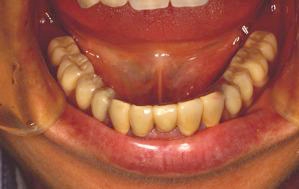

術後口腔内(正面観)もう入れ歯は要らなくなりました。